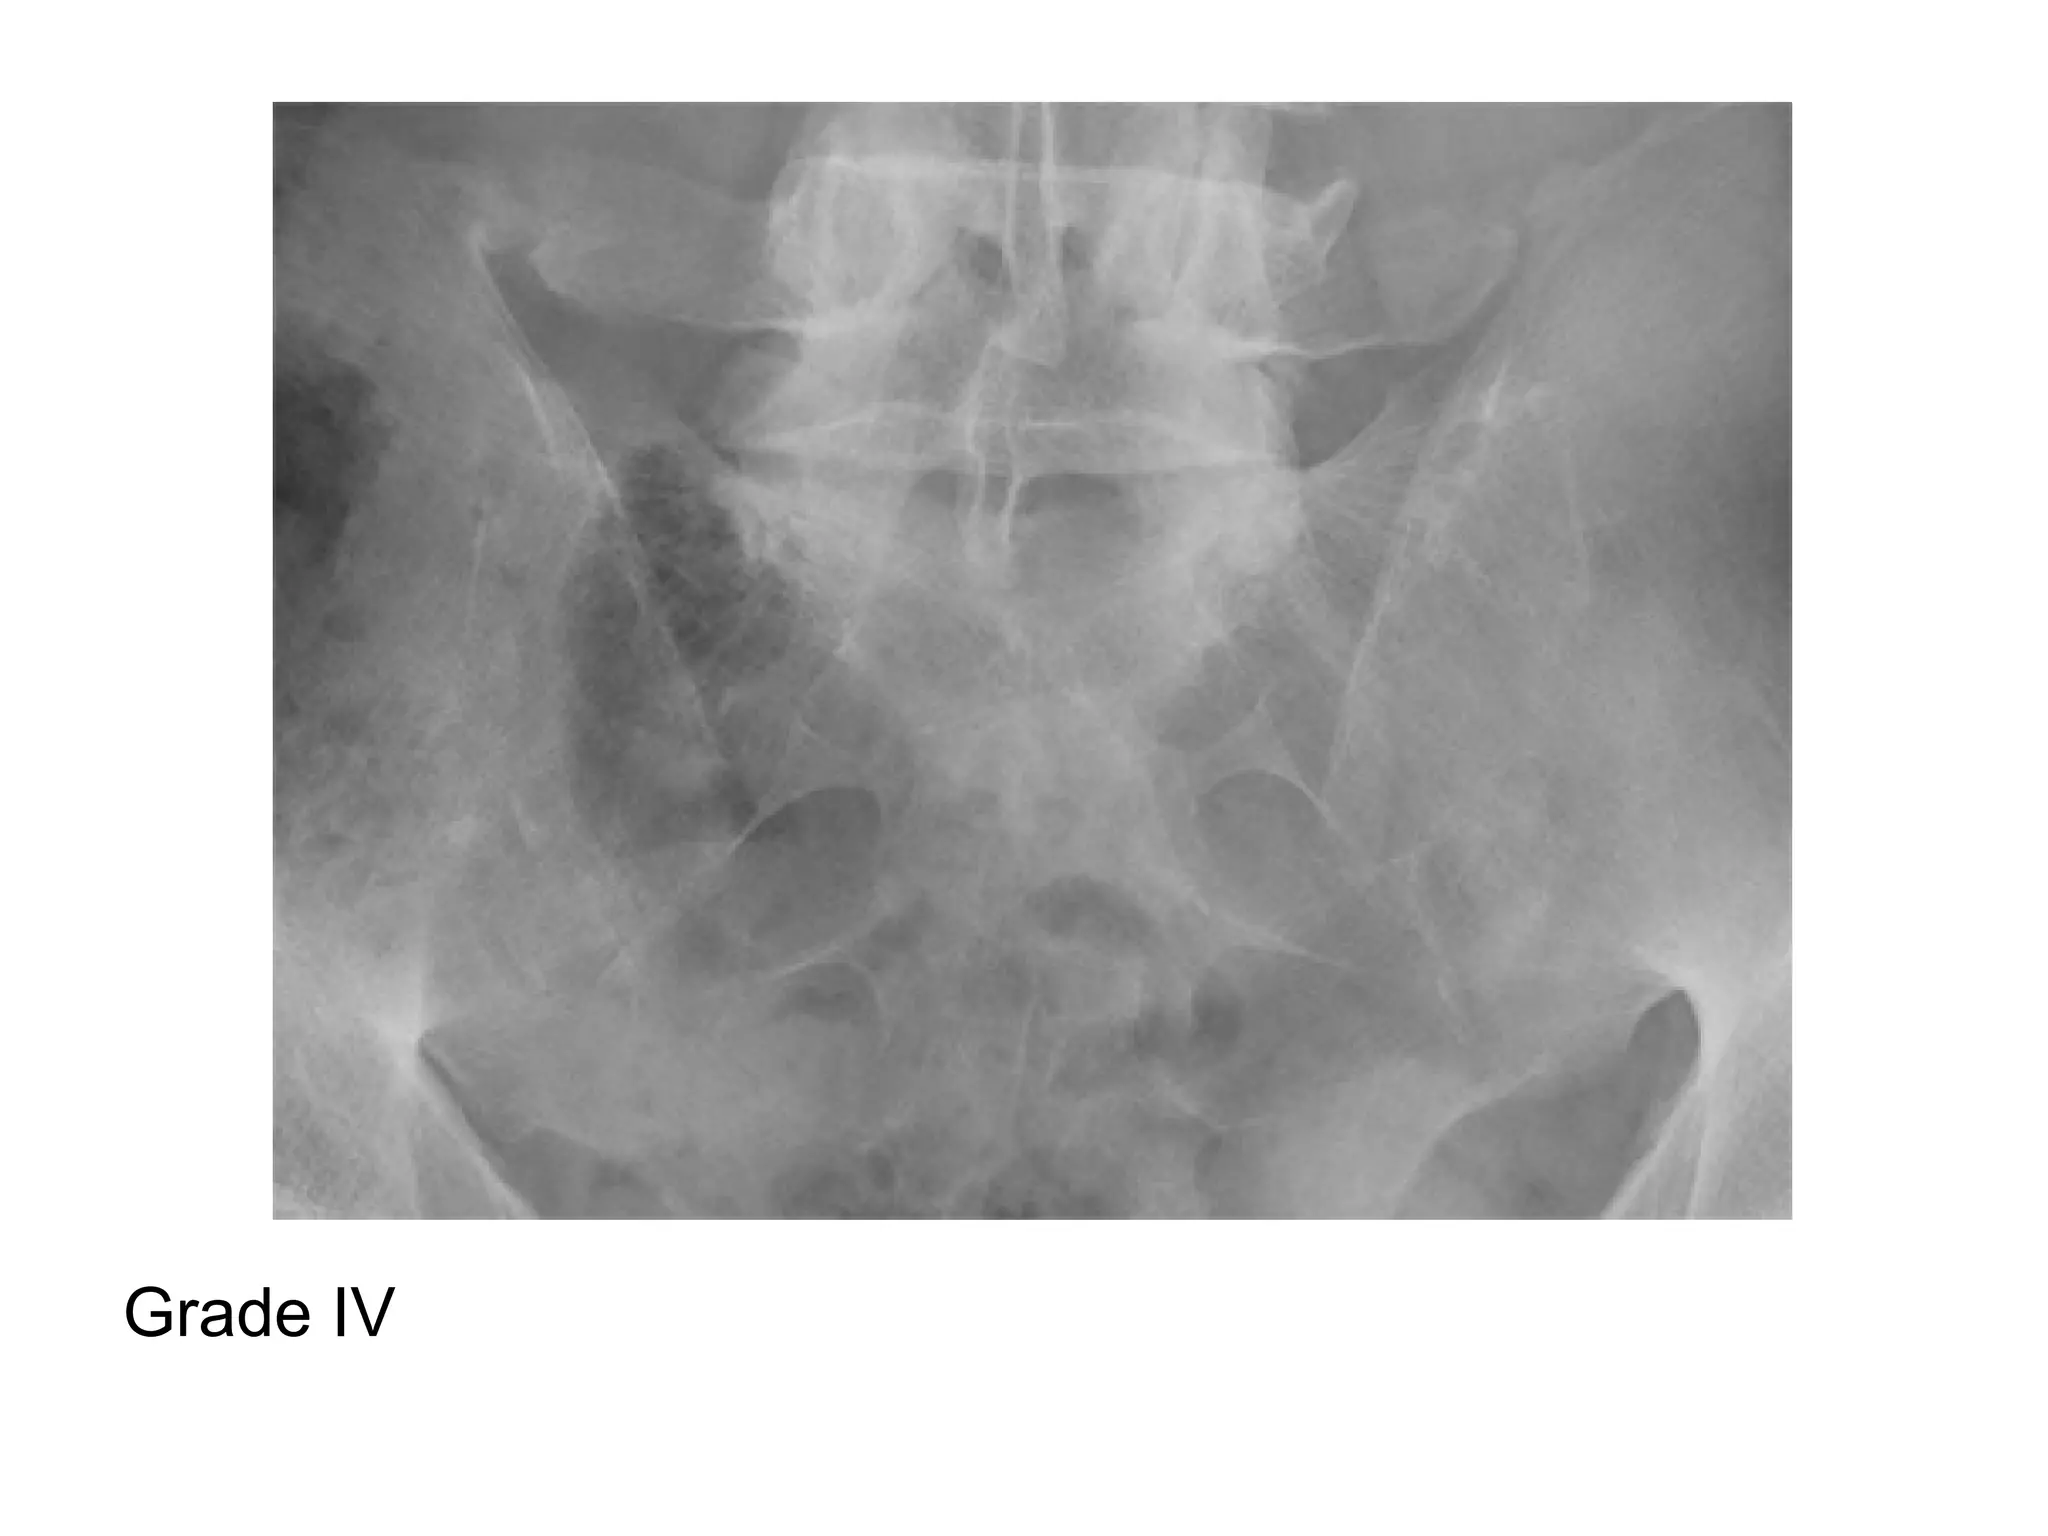

-Grading of Sacroilitis :

*Grade 0 : Normal

*Grade I : some blurring of the joint margins

suspicious

*Grade II : minimal sclerosis with some erosion

*Grade III : definite sclerosis on both sides of joint

with severe erosions with widening of joint space

with or without ankylosis

*Grade IV : complete ankylosis

Grade IV